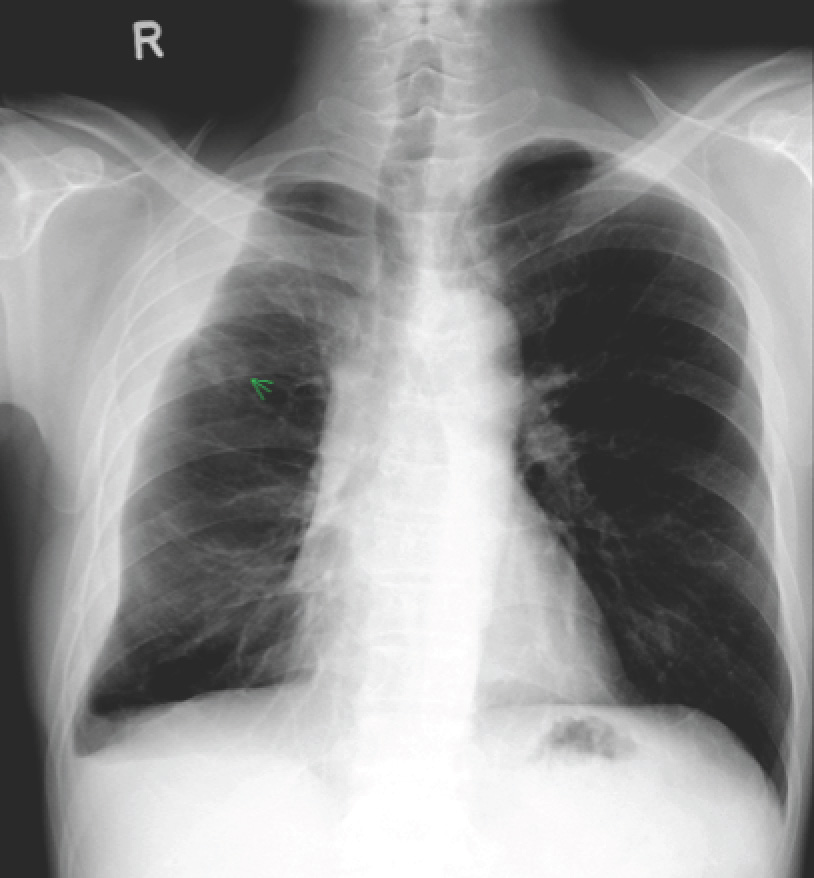

This patient had a loculated pleural effusion with radiological suggestion of a trapped lung. However, the massive increase in size of the pleural effusion 2 months after starting appropriate treatment is consistent with a paradoxical response to anti-tuberculosis therapy. This is now believed to be a immune reconstitution syndrome, and occurs in up to 15% of non-HIV patients but up to 25% of HIV-infected patients with concurrent tuberculosis who are started on highly-active anti-retroviral therapy (HAART). It occurs more commonly with extra-pulmonary tuberculosis, particularly cervical lymphadenitis and TB pleurisy.

Treatment of paradoxical response to anti-tuberculosis therapy is largely conservative, although steroids and/or surgical therapy are options if symptoms are severe. We offered the patient surgical drainage of the effusion in view of its massive size (potentially complicating respiratory function should any new lung infection develop), but he wisely refused. Subsequent chest X-rays showed gradual reduction in the size of the effusion over time, although it did not really disappear even at the time of stopping anti-tuberculosis therapy.